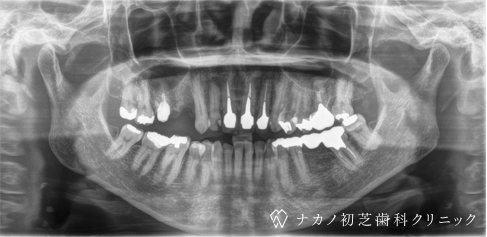

インプラント・7本 (60代男性)

-

BEFORE

AFTER

年齢 60代男性

治療内容 インプラント治療7本(骨造成の併用)

インプラント治療とは、歯を抜いた所にチタン製の人工歯根を埋入し、その上に歯を入れる方法です。骨を増やすことで、より審美的に治療が出来ました。費用 1本 400,000円(税込 440,000円)

リスク・副作用

腫れ・疼痛・違和感を感じるなどの症状を生じることがあります。